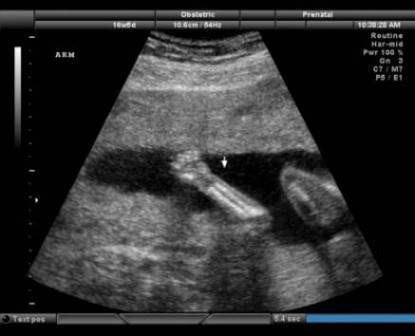

I genitali ormai quasi completamente formati, iniziano a diventare definiti, ed il feto misura ormai circa 15 centimetri.

- le gambe e le braccia assumono una proporzione organica rispetto al resto del corpo

- dal punto di vista del peso, il feto passa dai 250 gr ai 500 gr ed arriva ad essere lungo fino a 30 cm